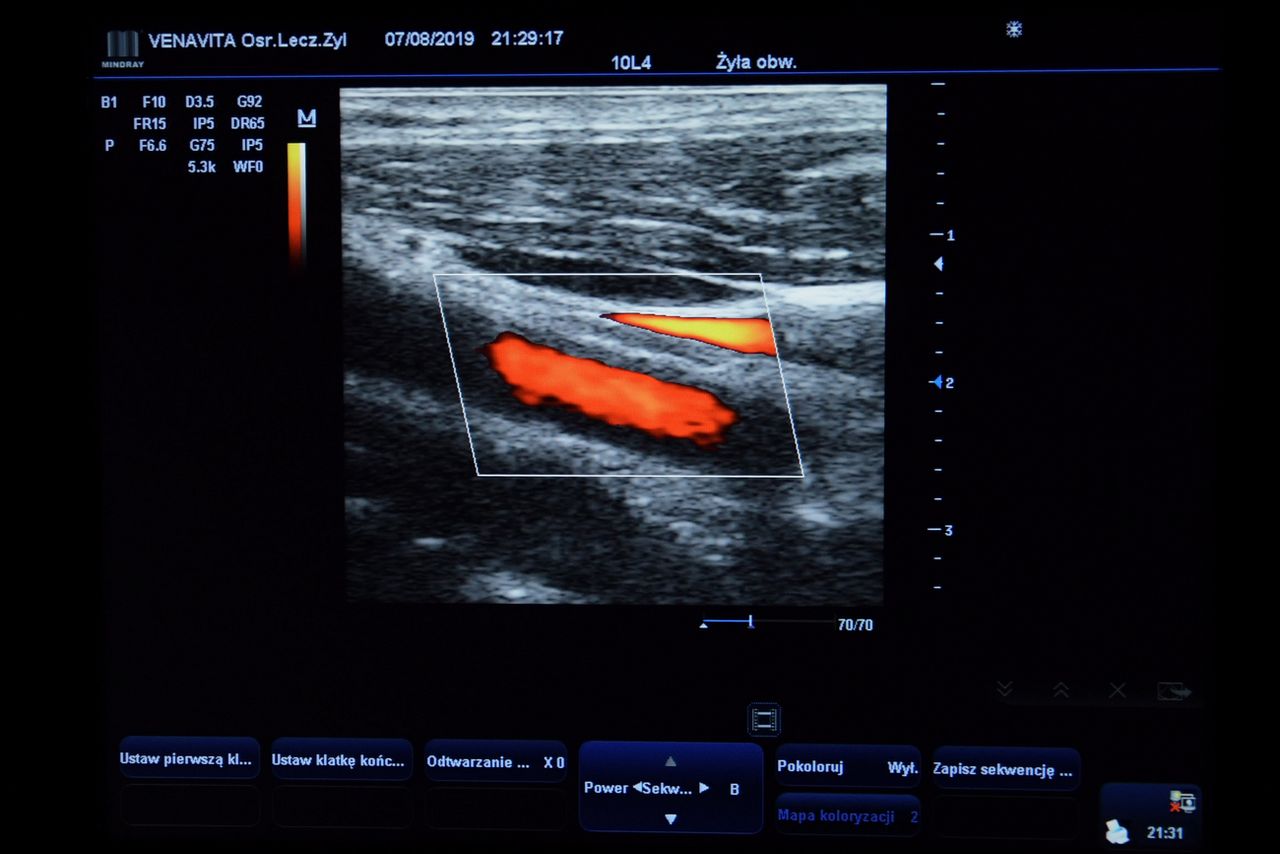

Podczas wizyty zawsze wykonuję badanie USG Doppler, które pozwala ocenić stan żył powierzchownych i głębokich, drożność naczyń oraz kierunek przepływu krwi. Jest to bezbolesne i bardzo ważne badanie – pomaga potwierdzić rozpoznanie, wykryć zakrzepicę i dobrać najbezpieczniejszą metodę leczenia. W razie potrzeby służy również do kontrolowania postępów terapii.